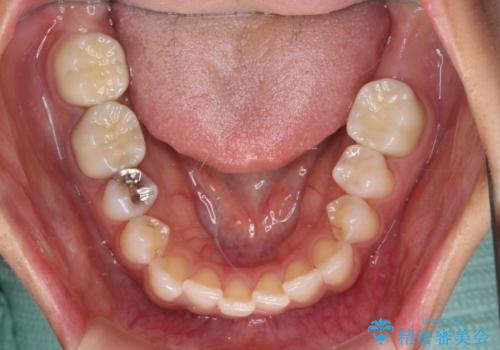

銀歯の下のむし歯については、優先度の高い方からセラミッククラウンなどで治療していくこととしました。

治療開始時は右上奥歯と前歯のみが気になっていたのですが、その後下顎左右の奥歯に強い痛みや銀歯の脱離などが頻発し、問題のあるところは全て治療を行うこととしました。